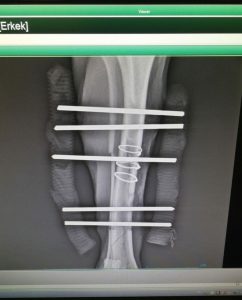

Klinikte gerekli kontrolleri yapıldıktan sonra mümkün olan en kısa zamanda ameliyata alınan köpeğimizin ameliyat sonrası röntgenini aşağıda görebilirsiniz.